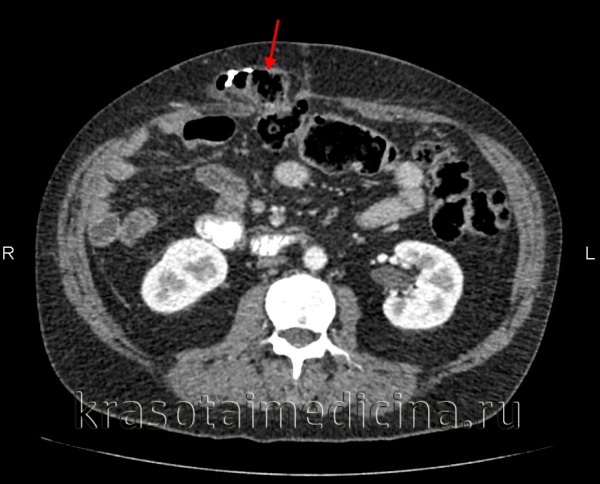

(Слева) На аксиальной нативной КТ определяется группа «инкапсулированных» петель тонкой кишки в левой половине брюшной полости. Обратите внимание на локализацию этих петель, тесно прилежащих к дистальным отделам двенадцатиперстной кишки, задней стенке желудка и ободочной кишке - в полном соответствии с местоположением парадуоденальной грыжи.